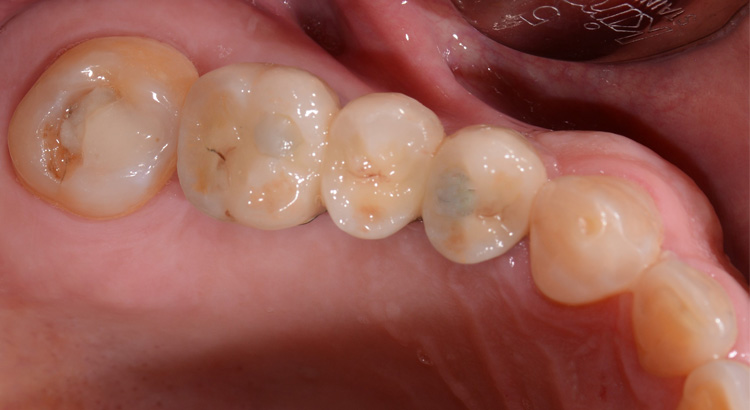

Protesi fissa su denti naturali

Il paziente presentava carie su tutti e tre gli elementi del settore posteriore, fondamentali per una corretta masticazione. La carie aveva portato ad una grave compromissione degli elementi, dolore dentale e il paziente masticava solo dall’altro lato. Grazie al trattamento endodontico e l’utilizzo delle nuove ceramiche è stato possibile ristabilire l’estetica e soprattutto la funzione masticatoria di quel lato.